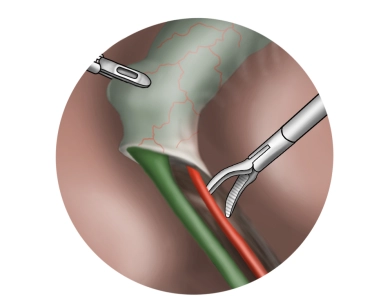

Escorrentía femoropoplítea y crural de la pierna

TEA de la bifurcación femoral, plastia con parche de la profunda, dilatación y colocación de stent de la A. femoralis superficialis izquierda